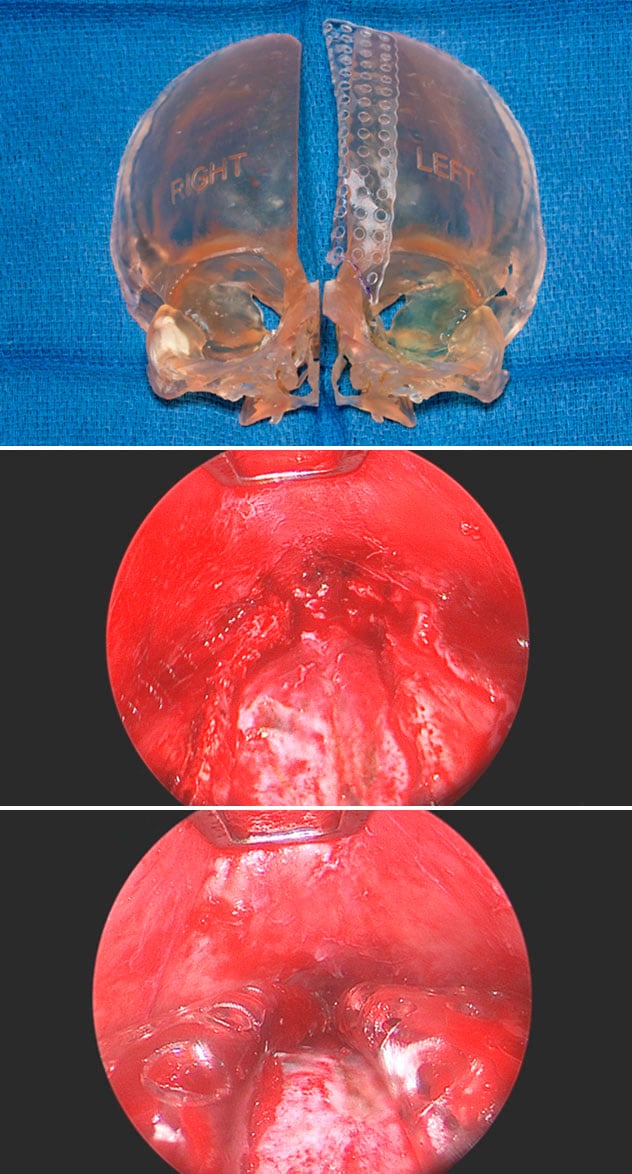

3D printed model of the skull (top) demonstrates suturectomy, followed by the application of an absorbable plate around the edge of the remaining bone. Endoscopic views of the suturectomy (middle) followed by the application of the absorbable plates (bottom).

At Mayo Clinic, a new approach helps some patients avoid helmet therapy after endoscopic surgery. Once the diseased cranial suture is removed, dissolvable plates are wrapped around the edges of the residual bone, to prevent refusion of the suture while the brain grows. The dissolvable plates have been used in other types of plastic surgery, such as cranial vault remodeling surgery. Their application to craniosynostosis arose from the clinical partnership of Drs. Ahn, Gibreel and Uldis Bite, M.D., a pediatric plastic and craniofacial surgeon at Mayo Clinic's campus in Minnesota.